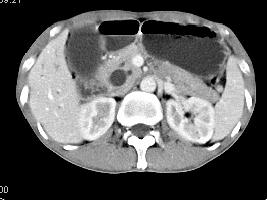

问题 男,48岁,进行性黄疸,发热,腹胀,影像检查如图,最佳的诊断是()

选项 A.胆总管囊肿 B.胆总管结石 C.胆总管癌 D.十二指肠乳头癌 E.胰头癌

答案 D